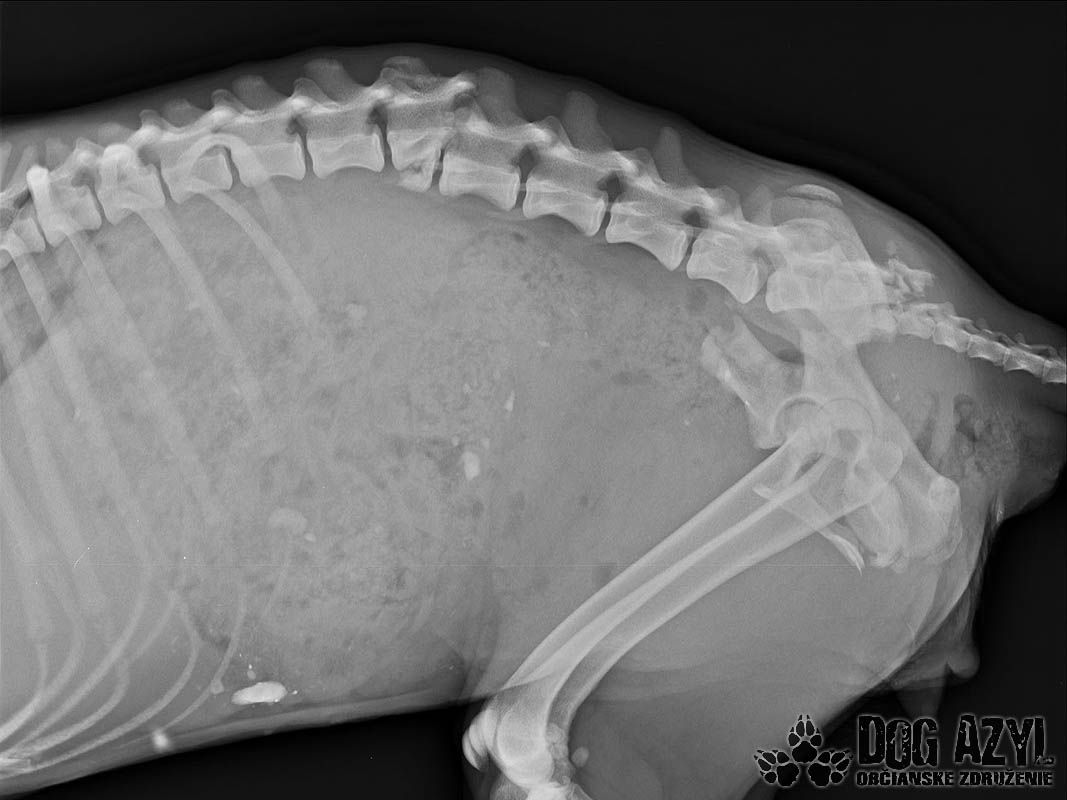

Mira, tak sme ju pomenovali.. Bola jednoducho úžasná.. Stalo sa však jedného dňa, že ju opustili.. Opustili a nechali napospas krutému osudu.. Nechápala a vybrala sa teda hľadať svojho človeka tam, kde ich bolo najviac.. Na vlakovú stanicu.. Vtedy ešte nepoznala ľudskú ľahostajnosť, iba lásku išla rozdávať.. Dni ubiehali jeden za druhým a nikto si po ňu neprišiel, nikto jej nepomohol.. Nenašiel sa ani jeden človek, ktorý by ju vzal do bezpečia pred rýchlym vakom.. V nepozornosti vybehla na koľajnice práve vtedy, keď vlak prichádzal.. Nie, ani po zrážke s vlakom jej nikto nepodal pomocnú ruku.. Musel ubehnúť týždeň, kým sa našla jediná dobrá duša, ktorá privolala pomoc.. Toto mladé a úchvatné dievčatko prežilo jeden celý týždeň s rozmliaždenou panvou, zlomenou chrbticou a poranenou miechou.. Neprestalo však čakať na svojho človeka, neprestávala dúfať, chcela žiť! Ľudia ju však iba obchádzali a odháňali..

Pomoc pre Miru žiaľ prišla neskoro.. Dnes poobede vraj ešte ako tak stála na nohách, ale večer okolo 22:00 keď sme dorazili, sa už postaviť nevedela. Našli sme ju zalezenú a premrznutú v plechovej búde.. Nedokázala si udržať stolicu, nedokázala sa samostatne vymočiť.. Miecha sa jej roztrhla.. Okamžite sme s ňou utekali do Bratislavy na kliniku, ale bolo neskoro.. Miruška musela mať neznesiteľné bolesti, ale tíško čakala a verila, lebo konečne bol pri nej človek, ktorého tak zúfalo hľadala..